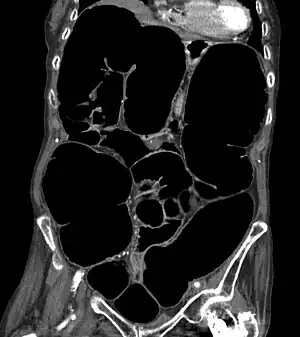

| CT scan of the abdomen of an elderly woman with Ogilvie syndrome | |

It generally occurs in those with significant health problems or following surgery.[2][1] While the underlying mechanism is unclear, it is believed to involve poor contraction of the colon.[3][1] Generally the cecum has a diameter of more than 10 cm and right colon is also dilated.[4] A CT scan or water-soluble enema is done to rule out a obstruction.[1]

Diagnosis starts with physical exam, observation, and interview of the patient. Imaging to diagnose dilation of the colon involves one view abdominal xray or obstruction series (PA chest, erect abdomen, and supine abdomen images). If further imaging is needed CT may be ordered.[13]